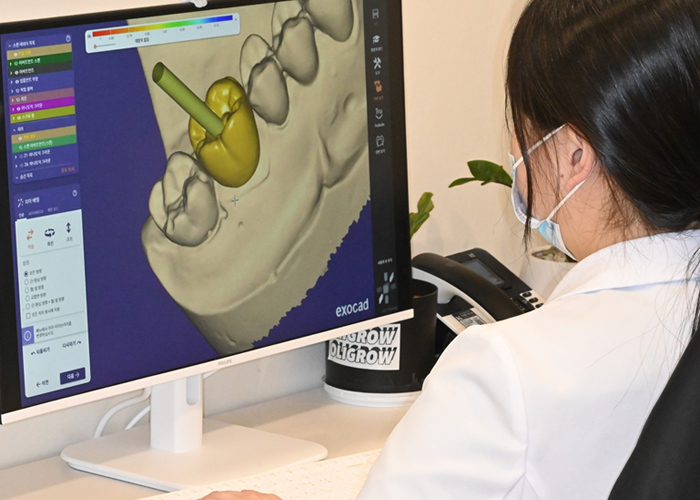

3D 디지털 정밀 진단

연세꿈꾸는치과에서는 치료 과정을 디지털 데이터를 통해 진행하여 실제 수술 전 3D 컴퓨터로 모의수술을 미리 보고 치료를 계획합니다.

고난이도 임플란트, 무절개 임플란트, 내비게이션 임플란트, 맞춤형 임플란트, 임플란트 재수술 등

풍부한 경험과 노하우로 3D 정밀진단 맞춤 솔루션을 제공합니다.